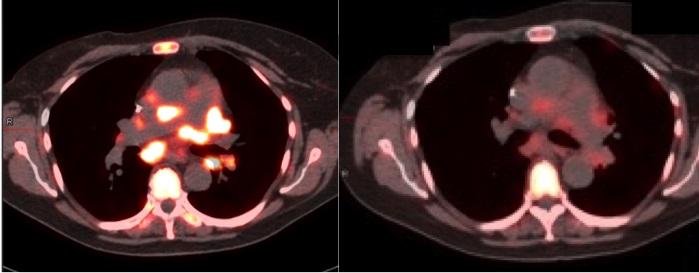

Unlike X-ray and ordinary magnetic resonance imaging (MRI), which reveal the large-scale structures of tissues in the body, molecular imaging uses special imaging "probe" compounds--injected into the patient--to highlight a desired molecular target in a tissue of interest. FDG-PET, one of the only molecular imaging techniques routinely used in oncology, employs a glucose-like probe, FDG, with a radioactive isotope of fluorine attached as a beacon. Once it is injected into the bloodstream, the FDG probe quickly accumulates in tumors, which tend to make heavy use of glucose. Thus, it "lights up" those tumors on a PET (positron emission tomography) scan.

FDG-PET, a method that the University of Pennsylvania helped pioneer, has been used for more than two decades to detect tumors and determine the extent to which cancer has spread. But the newer PET probes now in development and testing are meant for many other applications in cancer medicine.

Mankoff and his colleagues argue that making a strong clinical case for these new imaging techniques will mean demonstrating their ability to improve traditional treatment outcomes such as progression-free survival and quality of life. Clinical trials of these methods also could take into account the value of avoiding ineffective treatments. In one recent trial, researchers showed that a combination of FDG and HER2-targeted PET imaging was 100 percent accurate in predicting patient responses to a costly new anti-HER2 breast cancer drug.